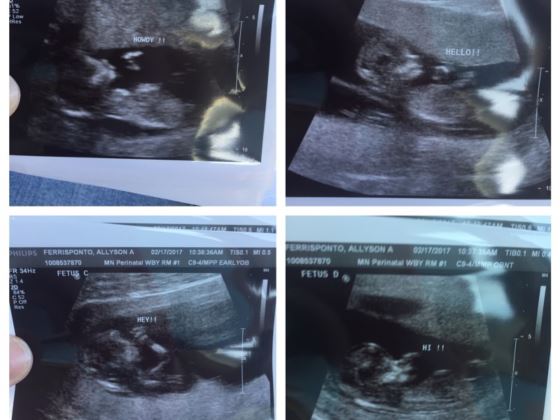

▼前5次人工受孕都失敗了,第6次人工受孕時,他們終於等來了好消息。為了肚子裡的孩子,Allyson非常注意,她心情忐忑去照超音波時,醫師開心告訴她,她肚子裡有4個心跳!

▼原來Allyson懷了四胞胎。她流產四次,這次上帝全都補償了回來。人工受孕不容易成功,所以會在母親體內多放置幾個胚胎,增加成功率。今年7月4日,Allyson通過剖腹產生下了4個女兒,女兒們都很可愛,也很健康。